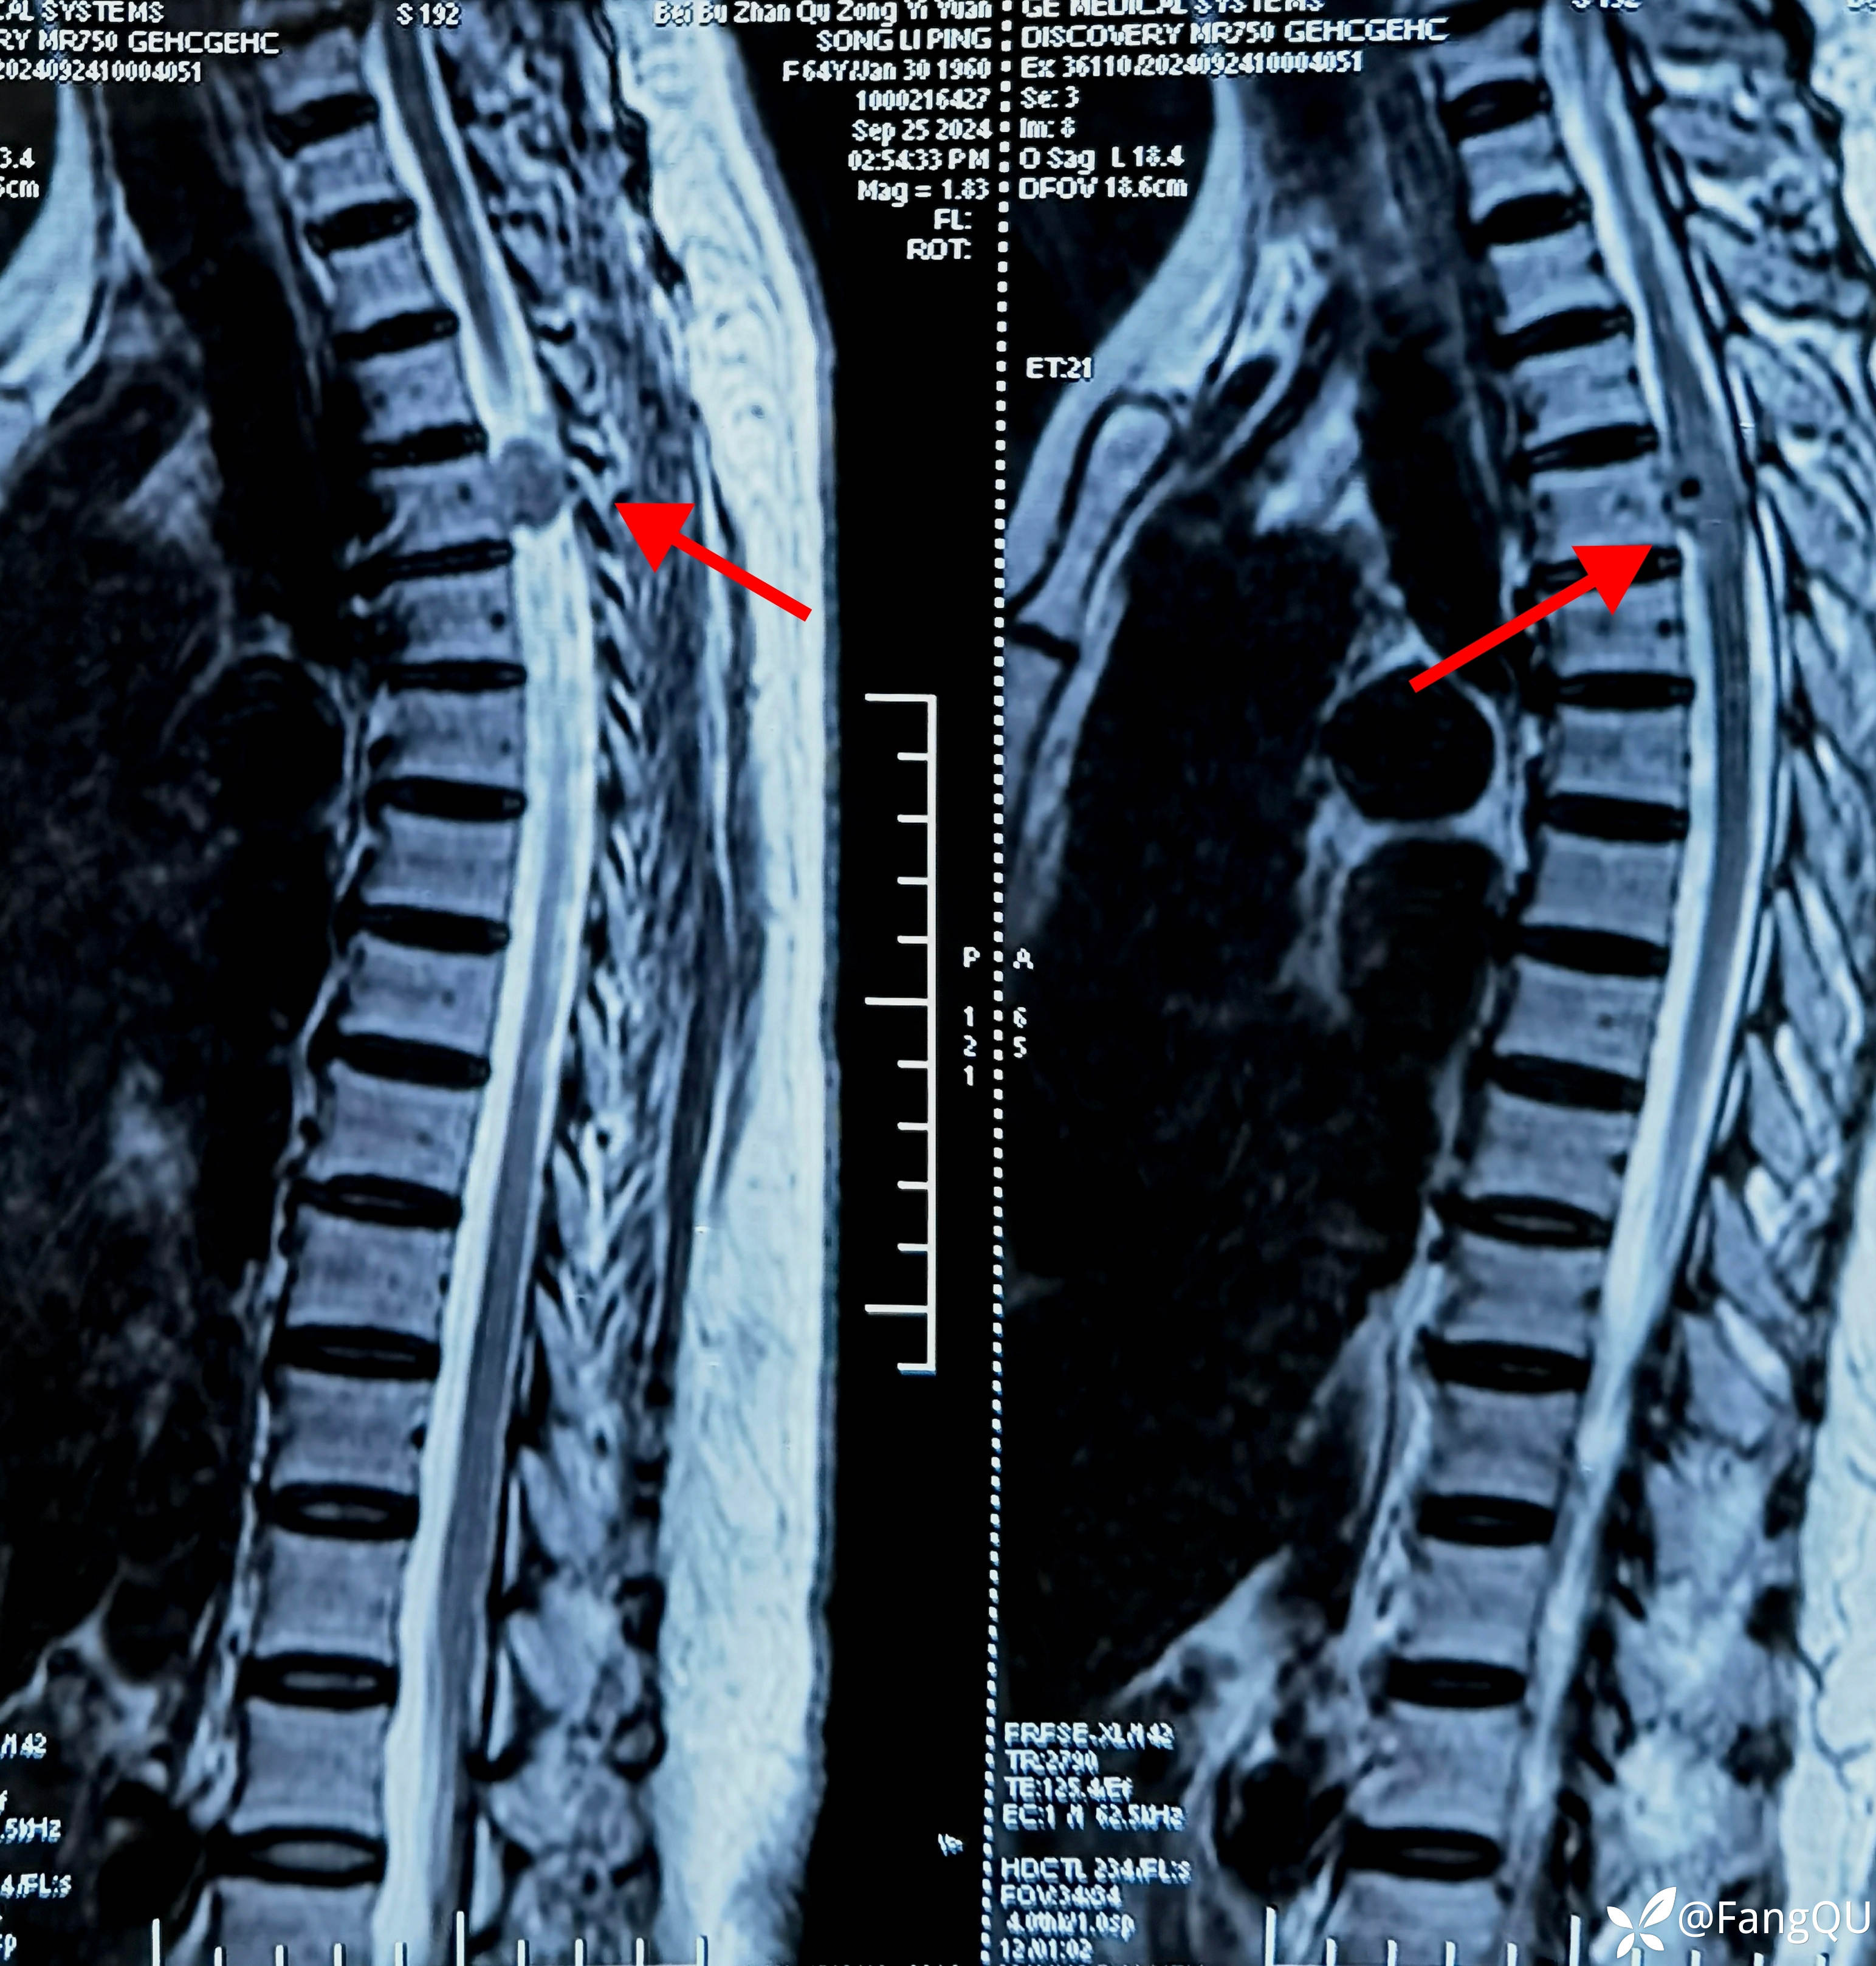

片子出来后家属复诊时说,这次终于找到病根啦,看到“占位”的字样没敢让病人知道也没敢带病人来门诊,胸椎MRI相当胸3节段脊髓信号异常,考虑髓外硬膜下病变?当然转给神经外科兄弟啦!